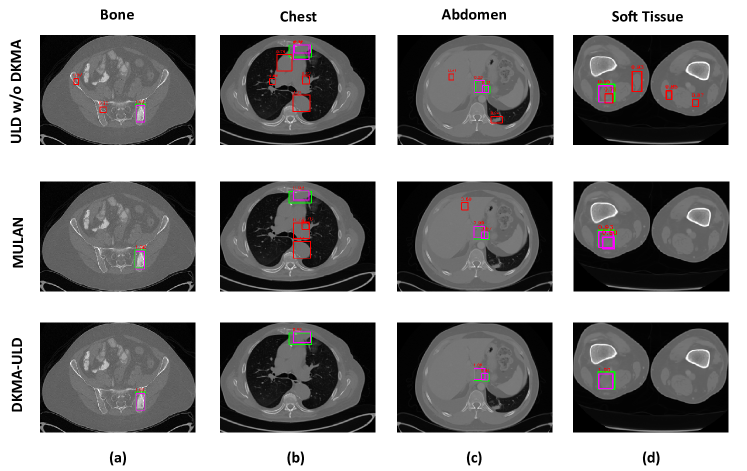

Figure 5: Qualitative comparison of DKMA-ULD and MULAN [Yan et al.(2019)] (at FP =222) on CT-scans of different body regions. The green, magenta, and red color boxes represent ground-truth, true-positive (TP), and false-positive (FP) lesion detection, respectively. Please note that ULD w/o DKMA represents when 3 slices with only one HU window ([1024,4096]10244096[1024,4096]), default anchors, and without convolution augmented multi-head attention feature fusion are used. We can observe that after incorporating domain knowledge in the form of multi-intensity CT slices, custom anchors, and multi-head attention (i.e., DKMA-ULD), the number of FP reduced drastically resulting in improved lesion detection performance as compared to MULAN.

Now, we present the ablation study on the introduction of different modules in the proposed lesion detection pipeline, as shown in Table 2. Our proposed 555 HU windows to give organ-specific domain knowledge results in an improvement of approximately 2%percent22\% in the average sensitivity (82.37%percent82.3782.37\%), as shown in row 3 of Table 2. Subsequent to this, we experiment with the inclusion of our novel convolution augmented multi-head attention module for feature fusion and custom anchors to detect varied-sized lesions effectively. We observe a performance boost by achieving an average sensitivity of 84.23%percent84.2384.23\%. All the ablation experiments are performed on CT-slices without applying cropping during the pre-processing step. Later in our experiments, we replace our feature extraction backbone with ResNeXt-152 and clip black borders in CT slices enabling the network to focus only on the region of interest. This resulted in a quantitative improvement by achieving a state-of-the-art average sensitivity of 86.88%percent86.8886.88\%. Finally, we show a qualitative comparison of lesion detection performance of our proposed DKMA-ULD in the form of reduction of FP in Figure 5. For more detailed experimental results, please refer supplementary material.